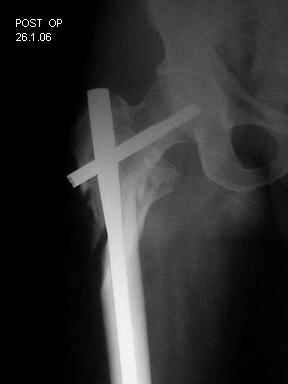

Few days ago I have posted an x-ray of severely comminuted Trochenteric # of Lt. Femur with sub-trochenteric extension of a male patient aged 65 years for opinion of fixation. Eight of you have kindly replied........

I choose Long Gamma Nailing and did it on 24.1.2006.

Now posting the post op x-rays for all of yours comments please. Don't hesitate to criticize me.

Congratulations. Virtually perfect. What reduction technique did you use? Looks like still traction table? To cavil to at least something looks like reduction is in microscopic varus - comparative x-rays can clear this - though only for academic interest with no clinical significance. Did you insert distal screws?